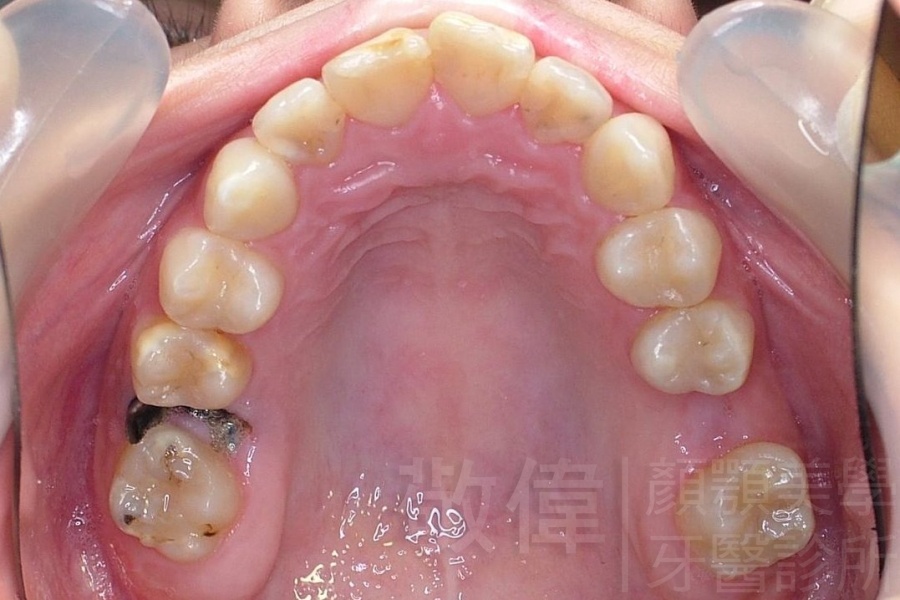

齒顏矯正/戽斗、亂牙、爛牙,變身 免植牙的健牙美女

<個案說明>

變臉矯正,原來戽斗妹跟大歪臉變成自信正妹

經由本院3D數影X光影像儀分析、與3D齒顎顏矯正技術,再配合口腔顎面正顎專科醫師施以正顎手術治療,雙方共同合作,使患者臉部外觀有很好的改善,大歪變小歪,產生了天南地北的大改變,她的人生也整個變得不一樣。